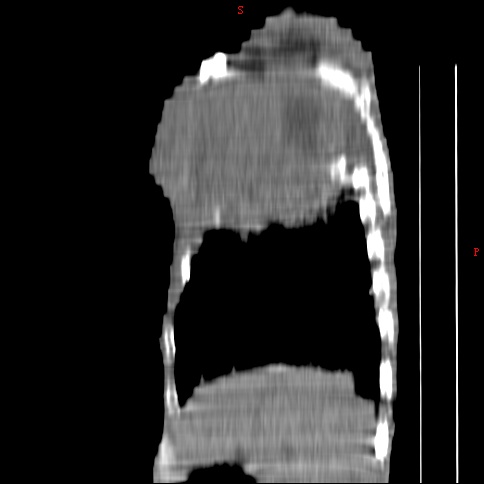

患者男,81岁,咳喘10余年,继往结核病史,发现胸部体表肿物(具体时间不详)就诊

右侧胸廓塌陷。右前上外侧胸壁软组织肿块,其内见有低密度影,肋骨呈溶骨性表现。右肺上叶见大量的间质纤维化表现。右侧膈肌上抬。

患者男,81岁,咳喘10余年,继往结核病史,发现胸部体表肿物

考虑:1、继发性结核,右结核性胸膜炎伴胸壁结核性感染

2、右侧胸壁恶性肿瘤。

肺尖巨大肿块影阴,胸壁受侵肋骨破坏,肿块密度不均且穿破胸壁入皮下,应该是:肺上沟癌;由于肺内有斑片状播散病灶,因此不排除胸壁结核。

患者男,81岁,咳喘10余年,继往结核病史,发现胸部体表肿物。

考虑:1 右侧胸壁恶性肿瘤(多考虑:胸膜间皮瘤)。

2 继发性结核,右结核性胸膜炎伴胸壁结核性感染。